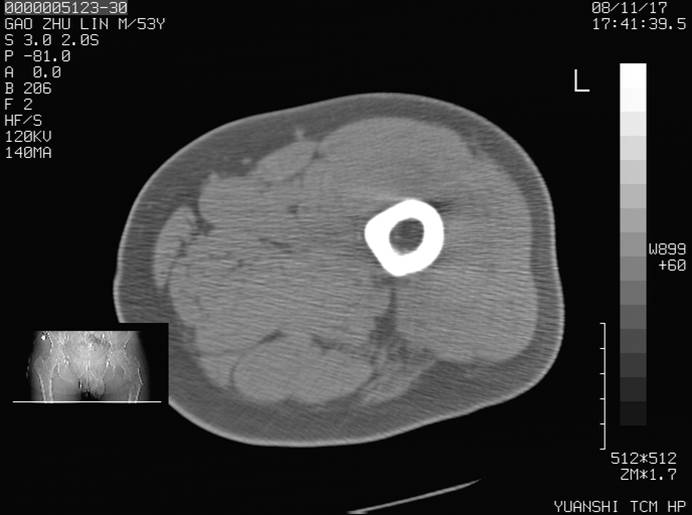

标题: CT16696:M53Y,左股骨上段骨折。 [打印本页]

标题: CT16696:M53Y,左股骨上段骨折。

左股骨上段外伤1个小时,左股骨上段疼痛。村医以腰椎间盘病变给以按摩及理疗数天。

图像不太清楚,左股骨上段外伤性骨折?病理性骨折?

左股骨上段粉碎性骨折

左股骨上段粉碎性骨折;建议上传骨窗看看是不是病理性的啊!

左股骨上段粉碎性骨折,不排除病理性骨折可能。

考虑骨肉瘤伴病理骨折

考虑:骨肉瘤伴病理骨折.

病理性骨折,考虑转移所致.